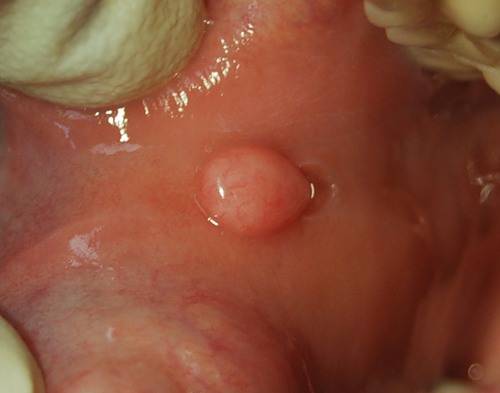

- Остроконечные кондиломы или просто кондиломы. Это бородавки вызваны плохой или отсутствующей гигиеной тела, чаще всего появляются в области паха, межъягодичной складки, а так же на половых органах. Выглядят как мягкие узелки или сосочки на «ножке», имеют розовый цвет.

- Сложный невус. Является промежуточной стадией пограничного и внутридермального невуса. Клетки новообразования находятся и в эпидермисе, и внутри дермы. Оно все еще имеет яркую окраску, но приподнято над поверхностью кожи в виде папулы или узелка.

- Внутридермальный невус. Полностью погружен в дерму. Здесь невусные клетки теряют способность накапливать пигмент меланин и постепенно светлеют. Такие невусы легко принять за папилломатозные образования, так как они часто имеют форму бородавки или располагаются на ножке.